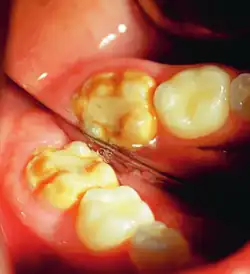

It occurs as a result of severe hypomineralization of the enamel as the enamel appears intact in the initial stages but gradually chips and fractures after the tooth erupts due to the weakened mineral content hence, leading to the formation of rough surfaces and cavities which makes the tooth highly vulnerable to undergo wear, decay and sensitivity.[26] Notably, the post-eruptive breakdown is linked to severe forms of hypomineralization like molar incisor hypomineralization (MIH).[27]

Enamel hypocalcification is characterized by the presence of white spots or streaks on the teeth due to reduced mineral content,[34] posing both cosmetic concerns and potential structural weaknesses. White spots can also be seen in patients. As the enamel undergoes demineralization, it becomes thinner, often leading to yellow or brown discoloration. The severity of this discoloration can range from mild yellowing to more pronounced brown staining, reflecting the extent of enamel loss.[7] This compromised enamel layer can also heighten tooth sensitivity to temperature changes and sugary foods, as external stimuli more easily reach the pulp, causing discomfort. Additionally, individuals with enamel hypocalcification experience a higher incidence of dental caries, as the weakened enamel provides less resistance to acid produced by oral bacteria.[19]

This compromised enamel is more susceptible to staining due to its rougher surface texture and increased permeability, which allows pigments and external elements to penetrate more easily. The weakened enamel may begin to wear away, especially on the occlusal surfaces of the molars, where mechanical forces are most intense. In some individuals affected by severe enamel hypocalcification, the structural deficiencies also contribute to anterior open bite where the upper and lower front teeth do not meet when biting down. This malocclusion can further complicate both functional and aesthetic aspects of the dentition.[37]